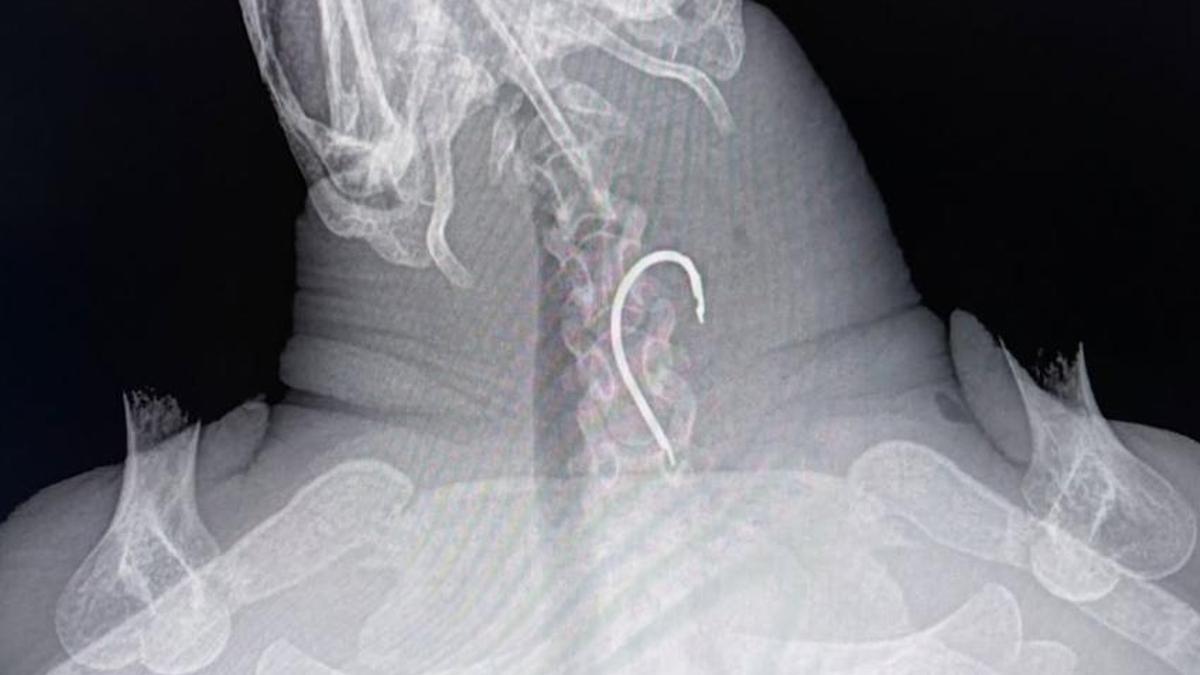

Radiografía del cuello de la tortuga antes de la operación. / Instagram Fundación Palma Aquarium

Durante una revisión mediante rayos X, los especialistas detectaron un anzuelo atrapado en su esófago. La operación, realizada con éxito por el veterinario Juan Ignacio Serra, de la Clínica La Vileta, permitió extraer el objeto sin causar daños graves.